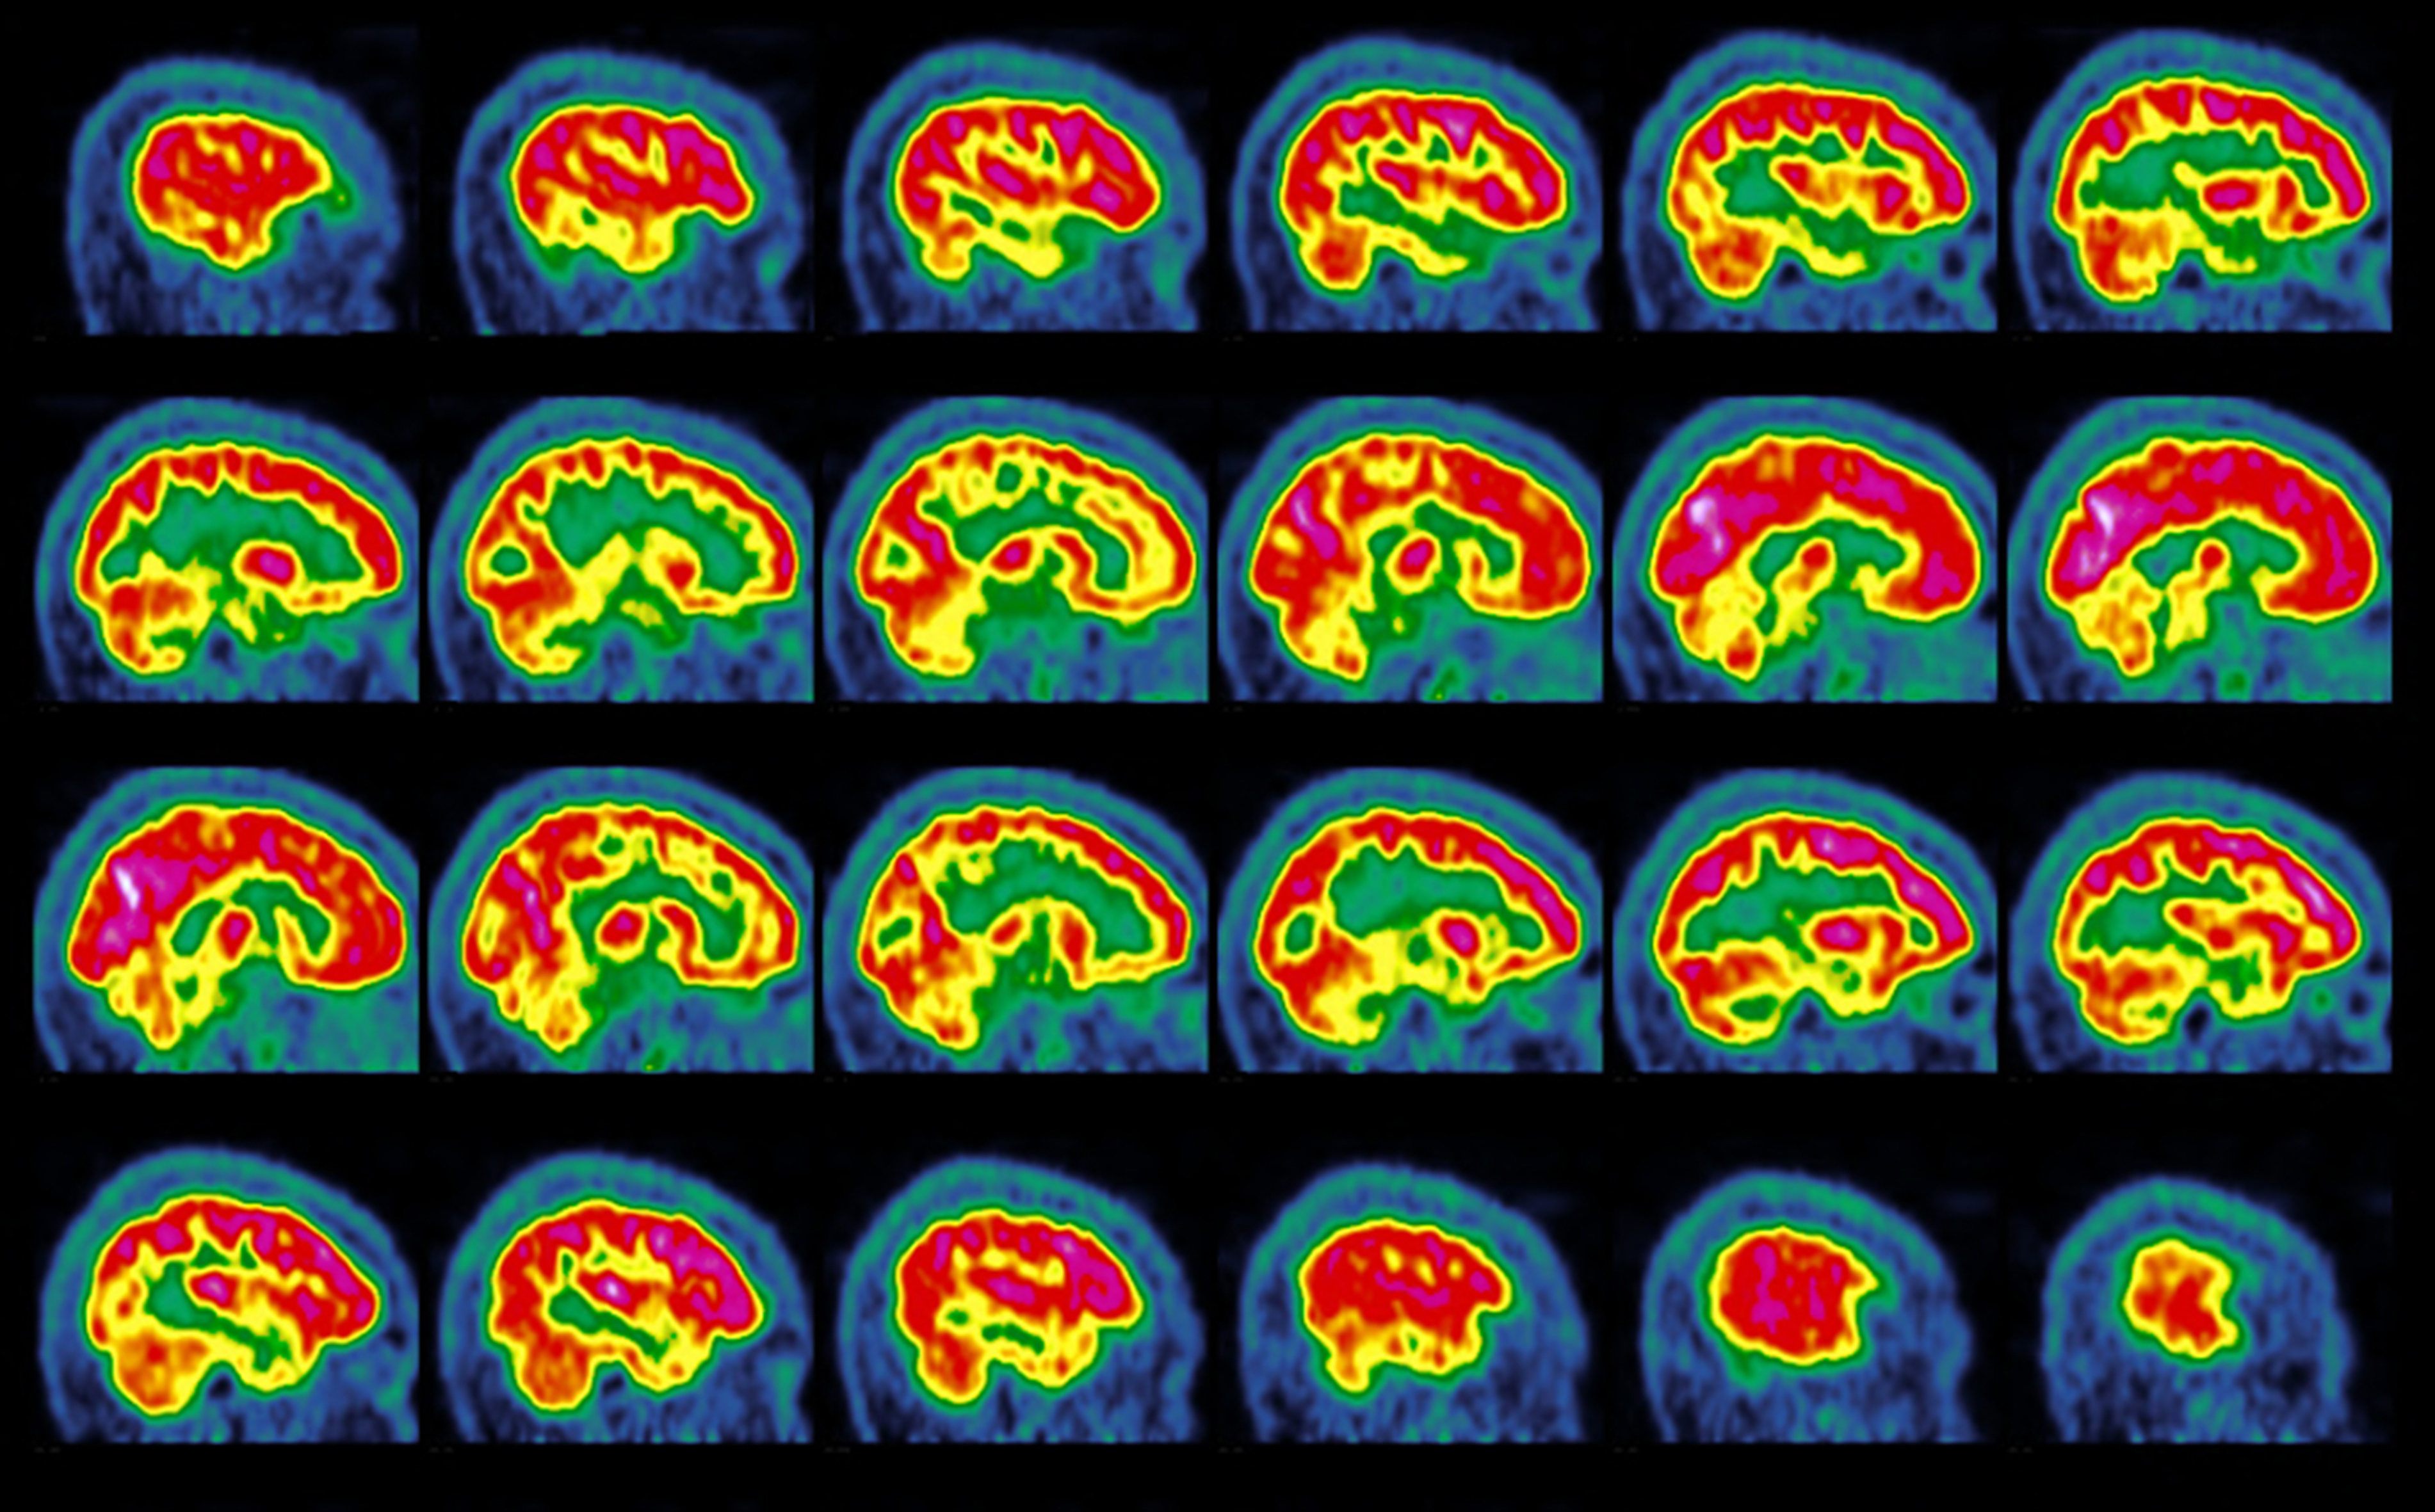

- The tool was trained on MRI and PET scans of 71 children and 23 adults with cortical dysplasia and focal epilepsy.

- By combining MRI and PET imaging, the detector reached success rates of 94% in one test group and 91% in another.